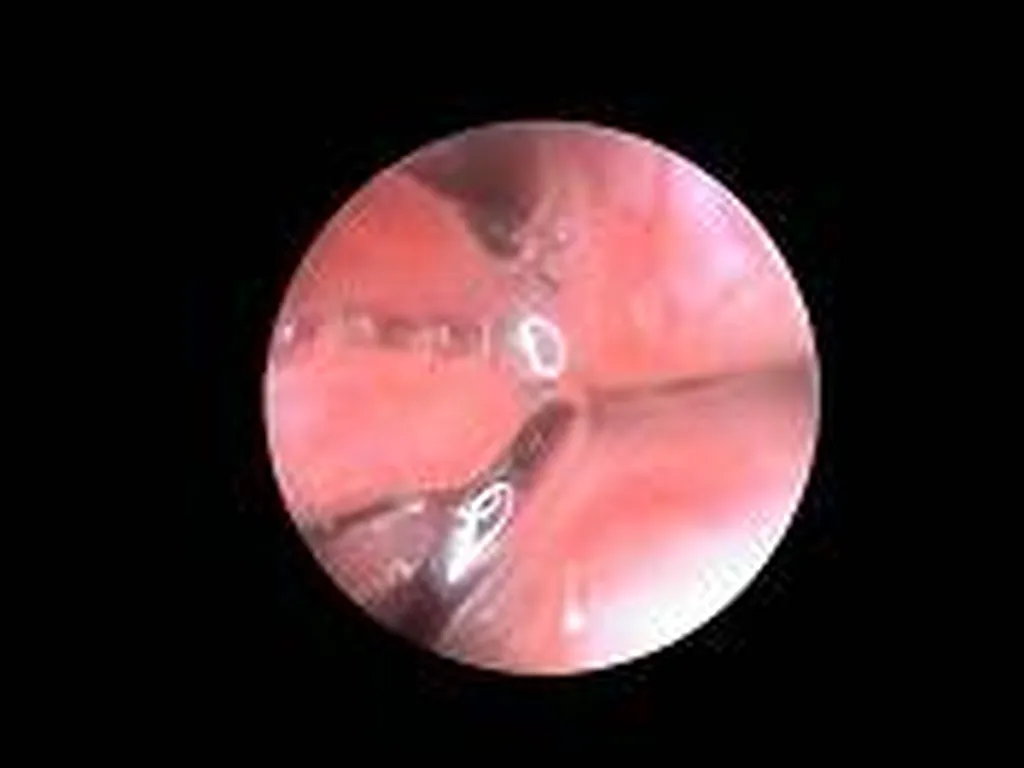

Affections touchant l’arbre respiratoire (endoscopie respiratoire) : corps étranger (épillet), paralysie laryngée collapsus trachéal, infection respiratoire bactérienne, fongique (aspergillose), parasitaire (angiostrongylose), tumeur.

Des clichés sont effectués tout au long de l’intervention afin que vous puissiez visualiser les affections notées au cours de l’examen.